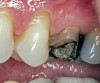

Replacement of existing restorations is responsible for 75% of all operative dentistry.15,19 The reasons for placement and replacement of restorations of direct restorative materials include: primary caries (Figure 1 and Figure 2); recurrent caries (Figure 3); poor margins (Figure 4 and Figure 5); restoration fracture (Figure 6 and Figure 7); tooth fracture (Figure 8); esthetics (Figure 9); non-carious tooth structure lost (attrition, abrasion, abfraction, erosion) (Figure 10); and pain/sensitivity.

Figure 4  Defective margins. Mandibular first molar with an amalgam restoration with defective margins.

Figure 4